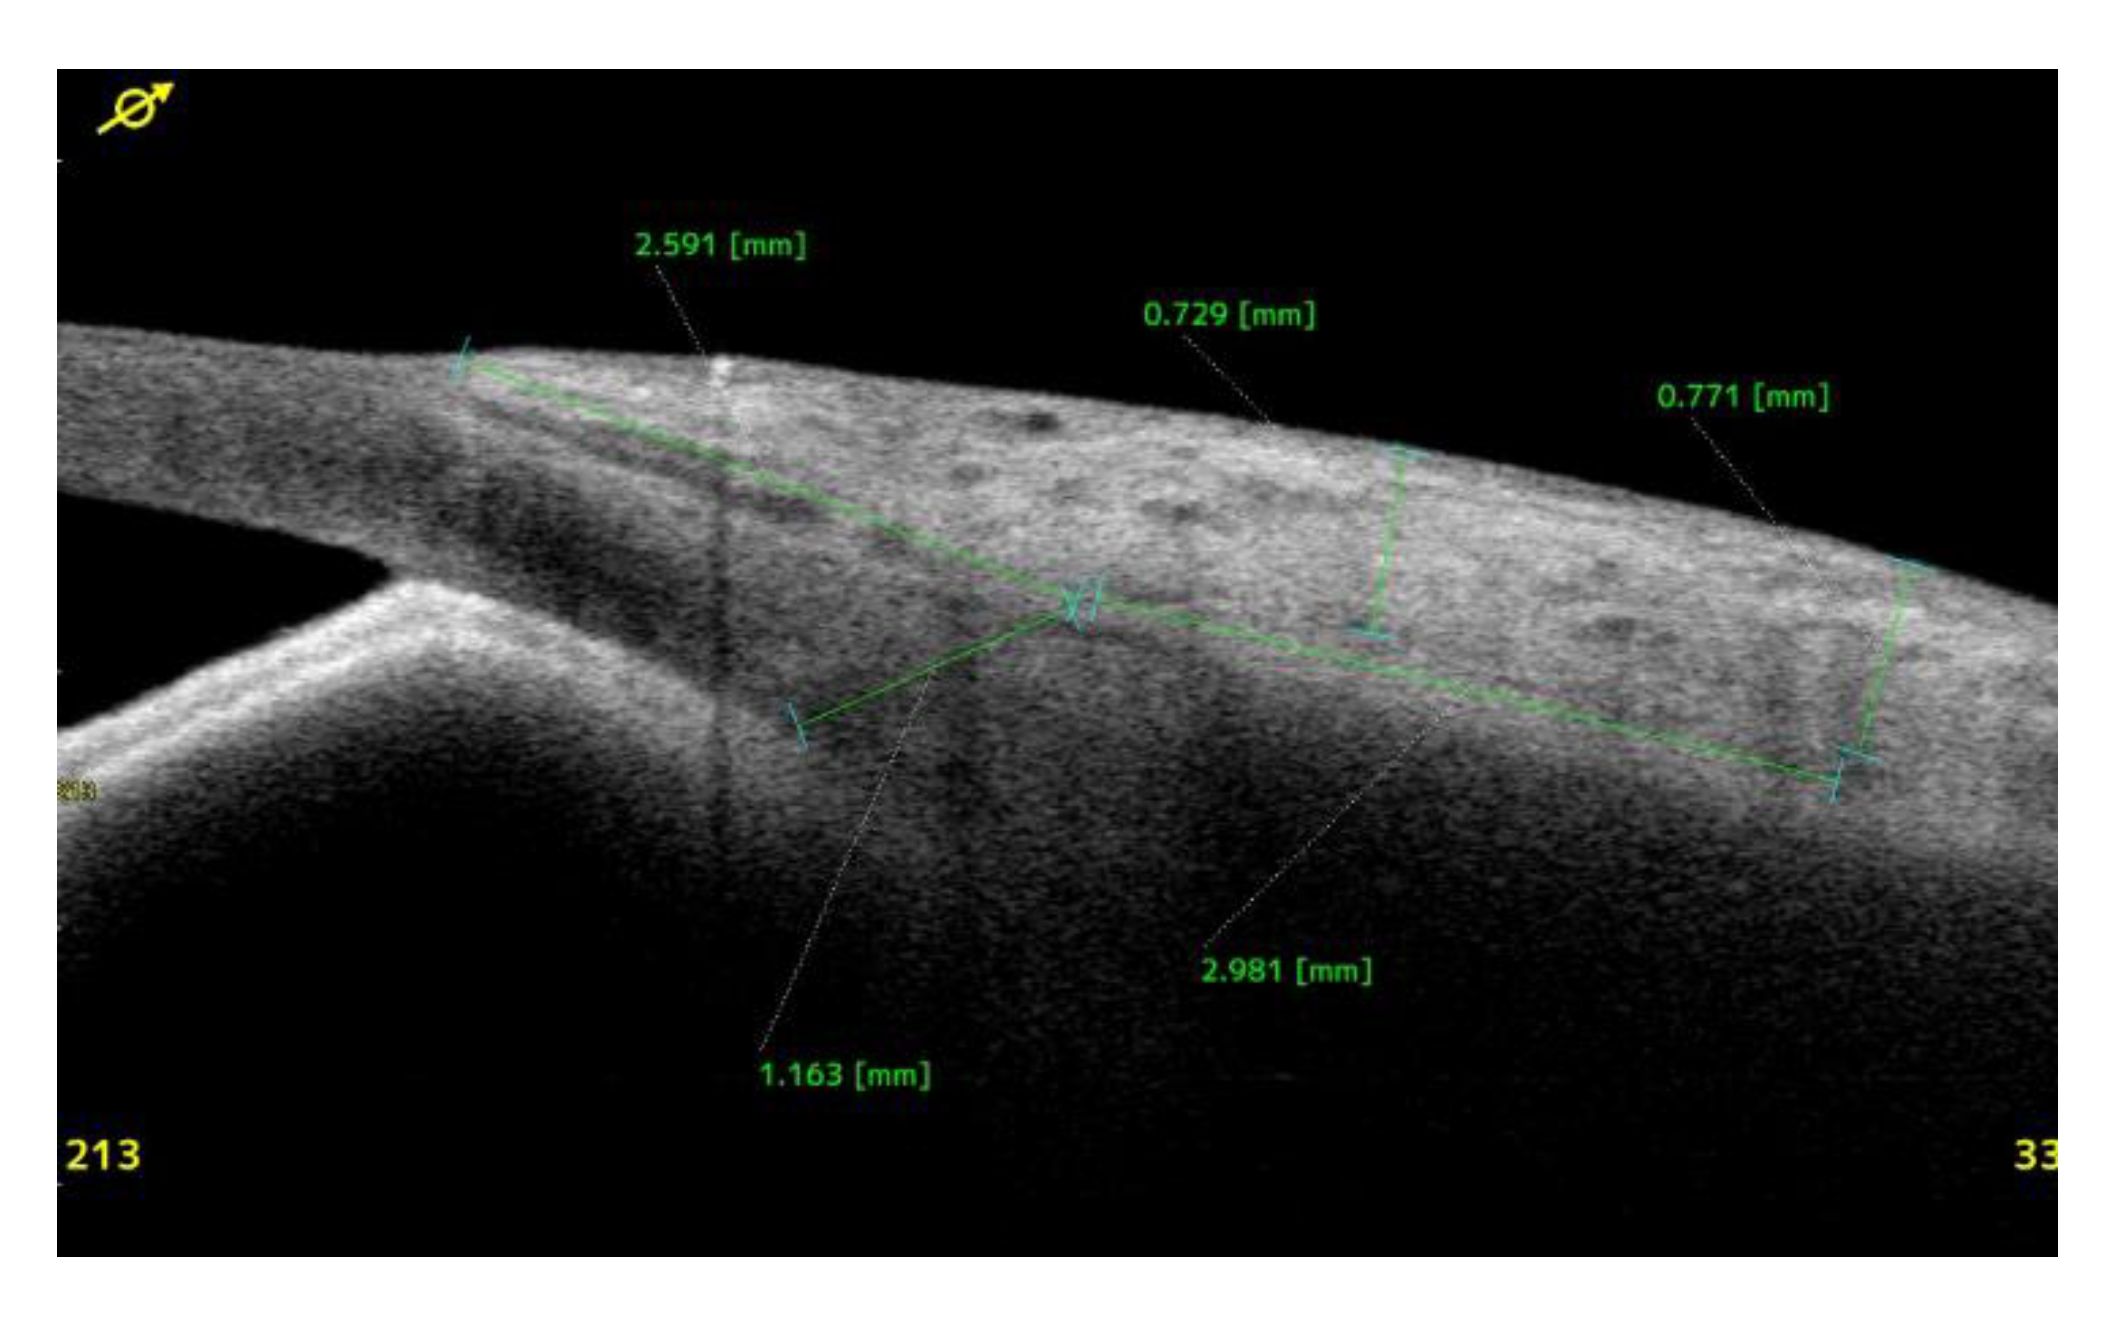

Clinical Course and Conjunctival Thickness in a Representative Case